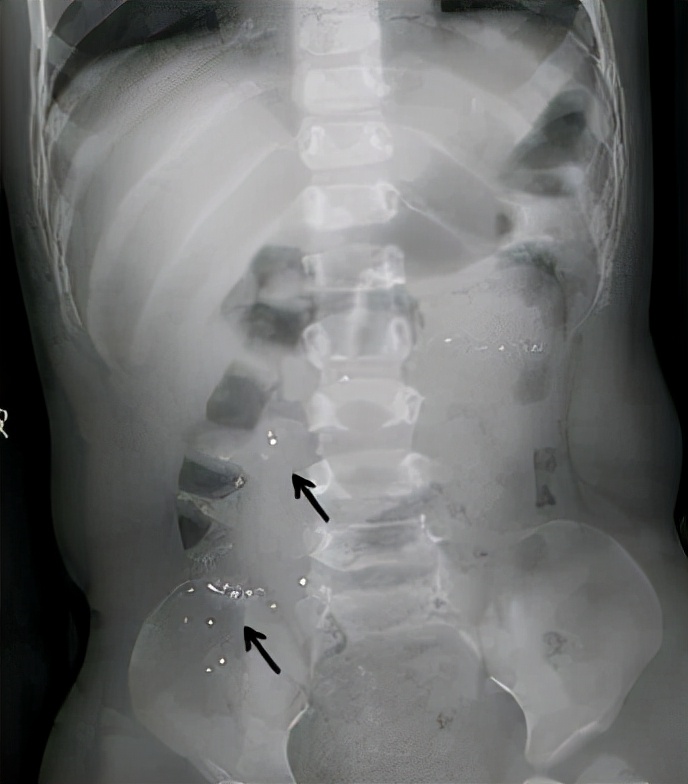

急忙之下,来影像科拍片检查,可以清楚看到肚子里的水银颗粒!

6、及时就医,必要时可以拍X线片观察下汞在胃肠道内的部位。